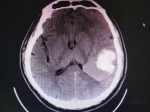

頭量、左側(cè)肢體活動(dòng)障礙小時(shí) 現(xiàn)病史【一般資料】男性,45歲,【主訴】頭量、左側(cè)肢體活動(dòng)障礙小時(shí)【現(xiàn)病史】患者家屬達(dá)患者于一個(gè)時(shí)前突發(fā)頭暈,左側(cè)肢體活動(dòng)障礙,血壓開高,無惡心嘔吐,未經(jīng)任何治府,在家人陪同下打車前來我院就診,診行頭部CT檢查,以“腦出血“收入我科系統(tǒng)治療【既往史】中年男性,高血壓病史一年,未治療。否認(rèn)糖尿病、冠心病史,否認(rèn)肝炎結(jié)核傳染病史,否認(rèn)藥物,食物過敏史,否認(rèn)外傷輸血史,免疫接種十劃進(jìn)行。【查體】T:36℃ ,P:76次/分,R:21次/分,BP:158/111/mmhg。意識(shí)清楚,語言流利,視物清楚,眼...